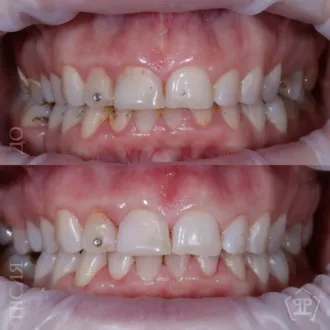

Результат коррекции металлической брекет-системой

Результат коррекции самолигирующей брекет-системой

Результат коррекции элайнерами

Результат коррекции керамической брекет-системой